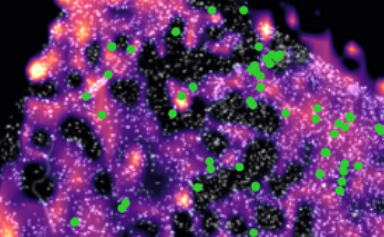

在另一组实验中,科学家们监测了具有IDH突变的人类胶质瘤肿瘤中的D-2HG和CD8+T细胞。他们发现D-2HG水平较高的肿瘤区域T细胞浸润水平较低,而T细胞较多的肿瘤区域D-2HG水平较低——这支持了小鼠模型的发现。“我们的结果表明,D-2HG可能不仅通过肿瘤细胞内在机制影响肿瘤的发生和生长,而且还通过直接影响周围TME中的细胞,”该团队指出。“我们建议D-2HG通过改变其代谢和细胞毒性特征直接作用于IDH突变肿瘤TME中的CD8+T细胞......我们的研究结果表明D-2HG改变CD8+T细胞中的葡萄糖代谢,导致增殖受损,细胞因子生产和细胞毒性。”